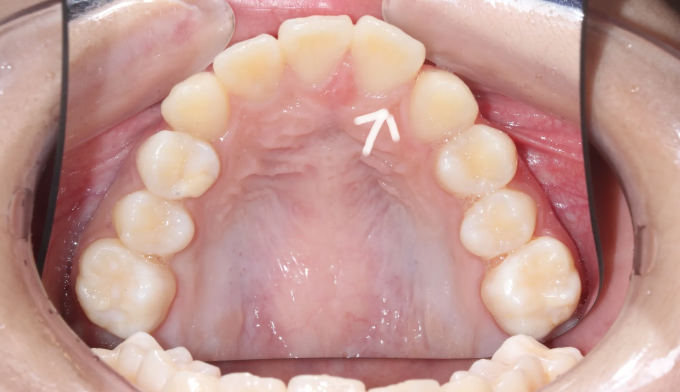

선천적으로 위 앞니 하나가 부족하여 치열이 틀어지게 된 경우입니다.(화살표 부위의 치아가 선천적으로 없습니다)